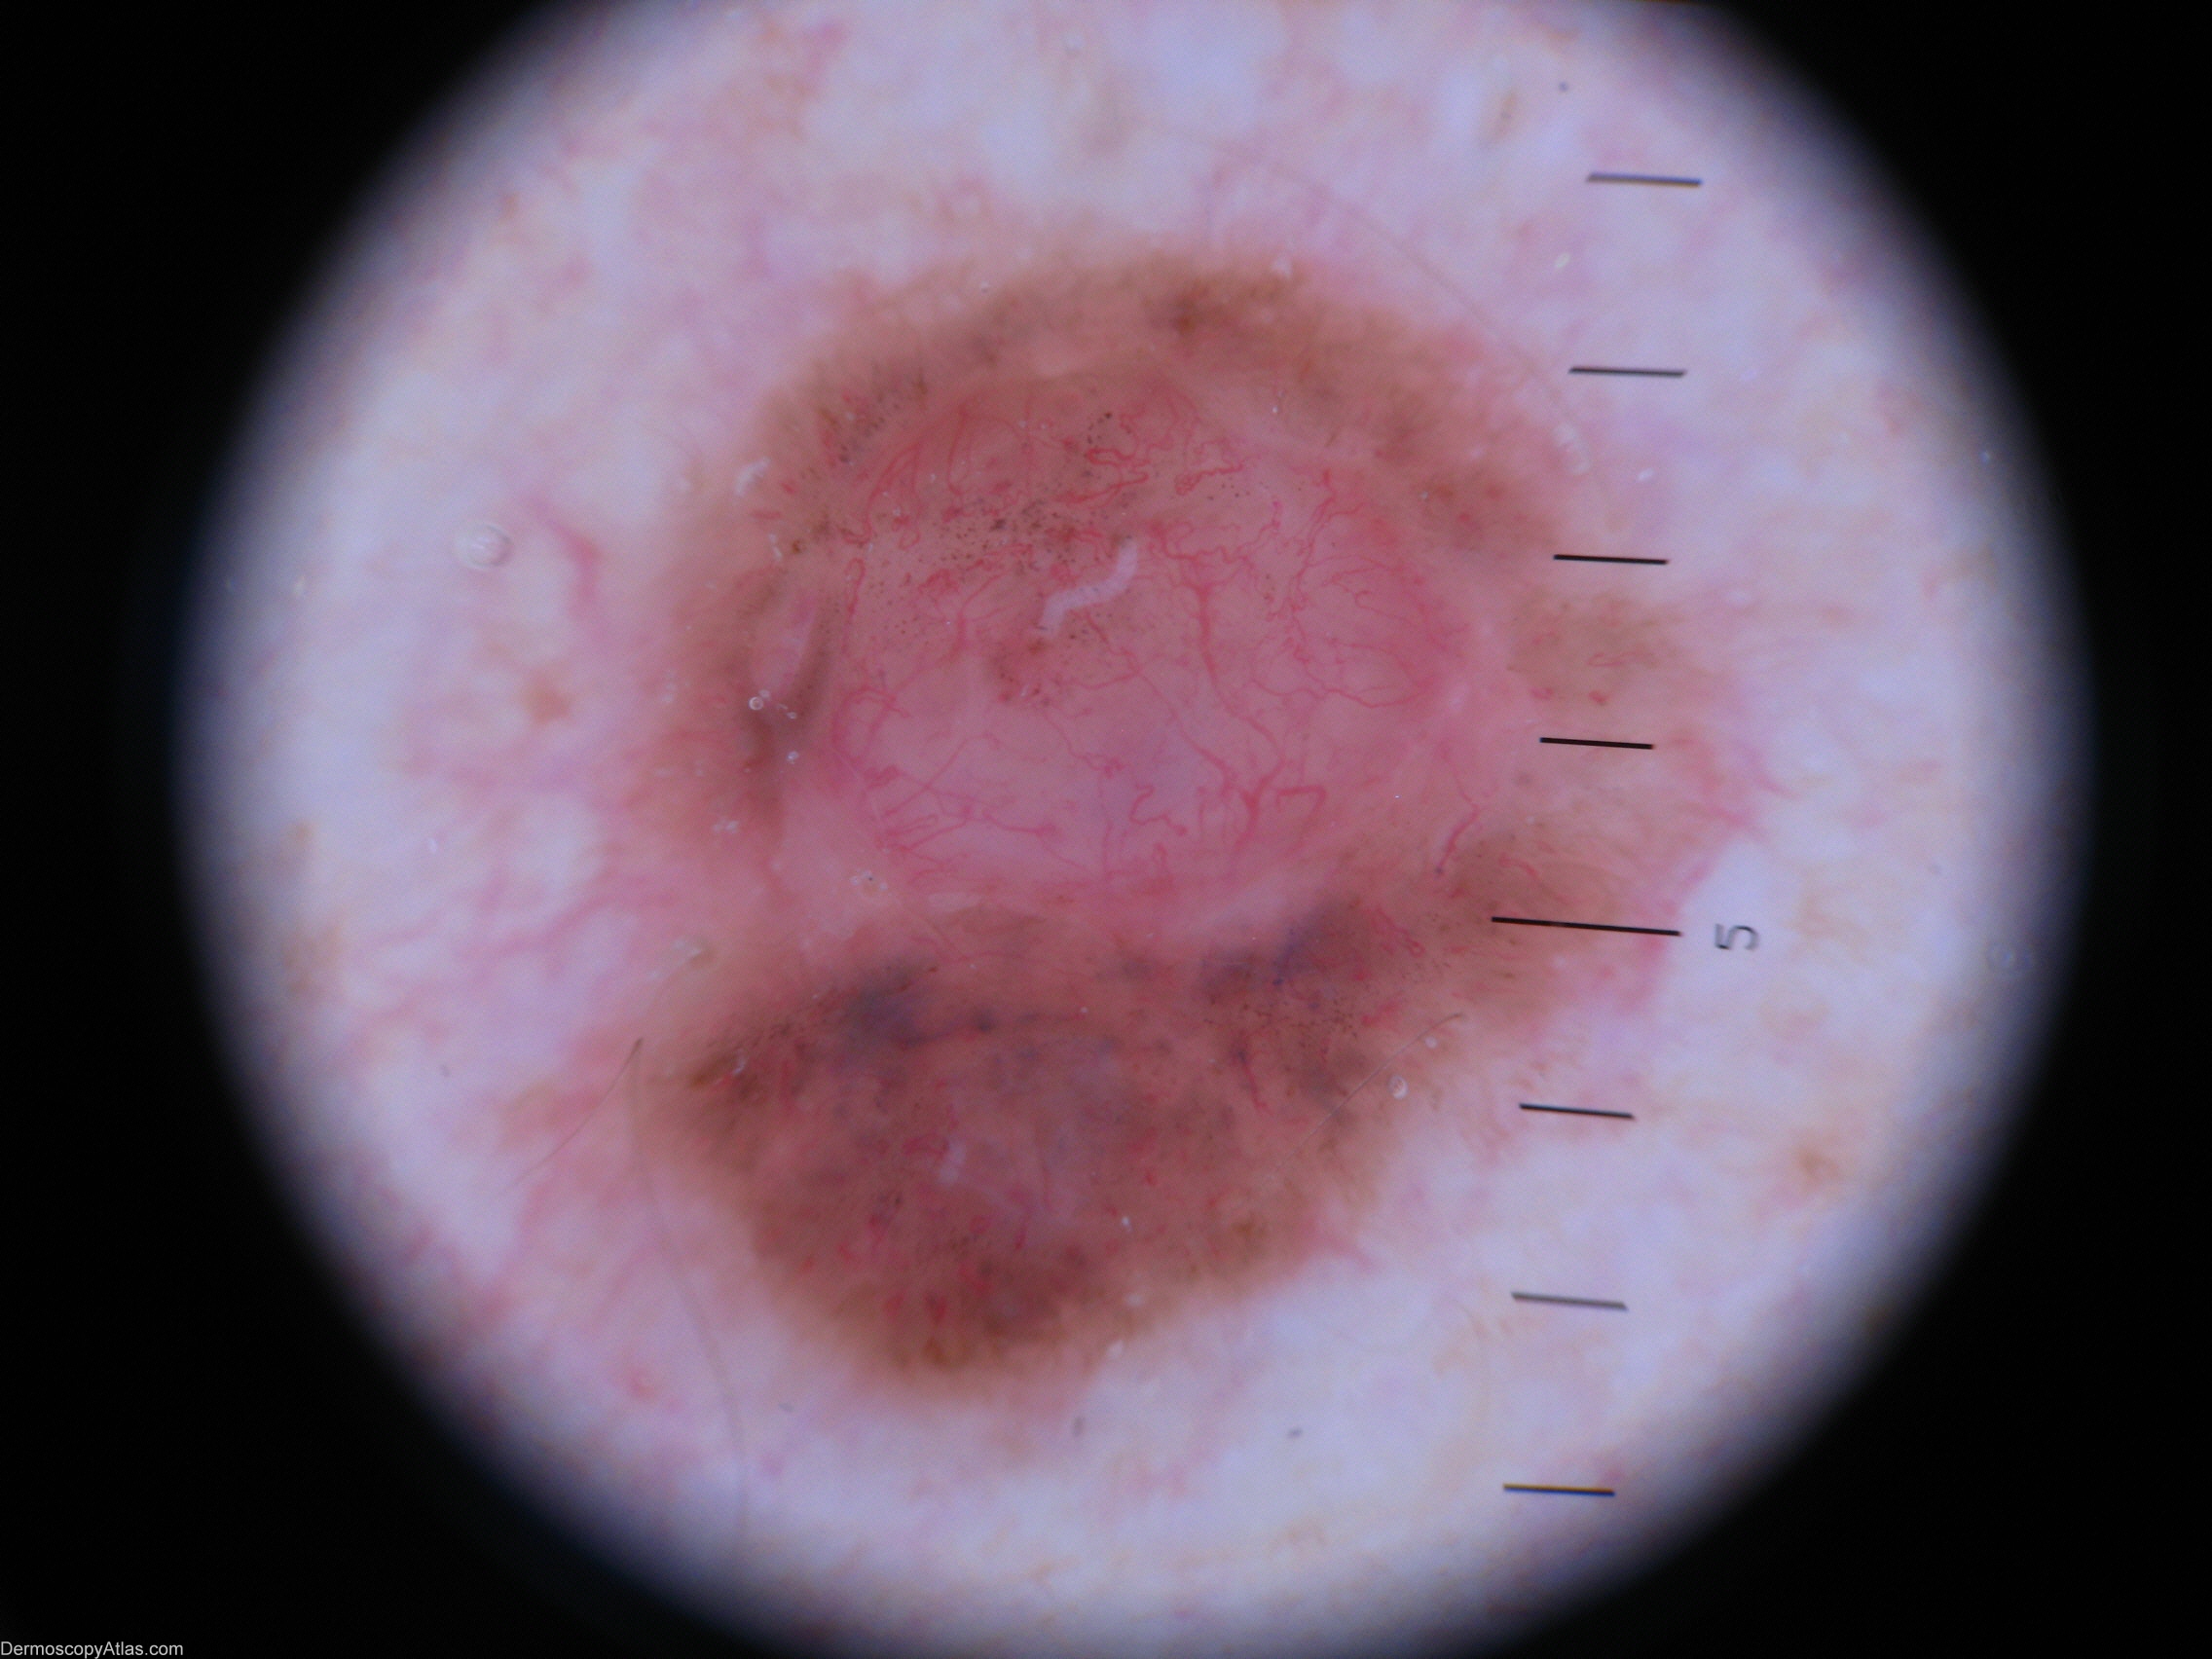

Site: Shoulder

Diagnosis: BCC pigmented

Sex: M

Age: 45

Description: Macro view

Patient was not worried about this lesion until his wife insisted he have it seen to.

It looked nodulocystic and seemed to be arising in a naevus.

Histology. Basal Cell Carcinoma (solid and pigmented)

Supplementary report revealed nearby associated Lentigo simplex.